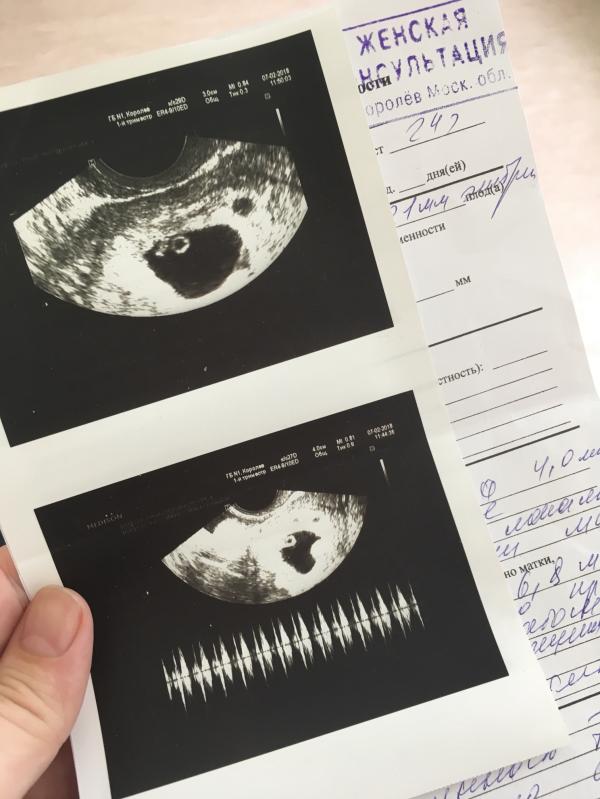

Наша первая фоточка😍

Положили в больничку,отдыхать)есть гипертонус и отслойка которая уже заживает🤞🏽Девчули,какое ЧСС у вас были на 7 недельке?